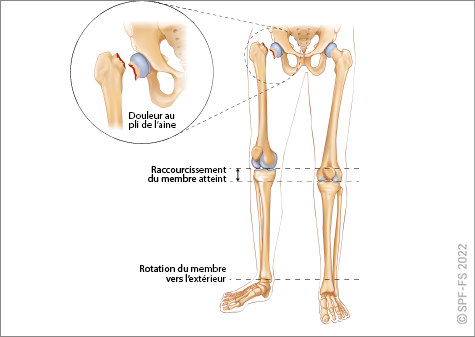

Les membres inférieurs

Les membres inférieurs sont chacun formés de trois segments :

Figure 2-13 : le membre inférieur

La hanche est l'articulation qui relie la cuisse au bassin. Le genou relie la cuisse à la jambe et la cheville la jambe au pied.

Ce dernier comporte cinq orteils numérotés de 1 à 5 de l'intérieur vers l'extérieur. Les phalanges sont numérotées de P1 à P3, dans le sens allant du talon vers l'ongle.

Figure 2-14 : coupe de l'articulation de la hanche